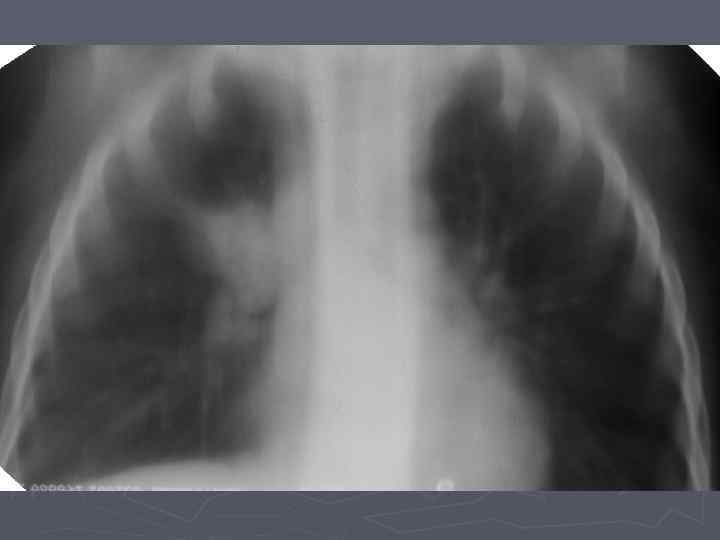

Клинические особенности туберкулеза у взрослых на фоне ВИЧ-инфекции ► ► ► ► ► Внутригрудные аденопатии; Милиарные высыпания; Частое поражение базальных сегментов легких; Относительно редкое поражение каудоапикальных сегментов легких; Распад легочной ткани диагностируется в 2 раза реже; Нередок плевральный выпот; Велика склонность к генерализации туберкулезной инфекции с множественными внелегочными локализациями. Присоеднинение туберкулезного менингита; МБТ в мокроте выявляются одинаково часто у ВИЧ негативных и позитивных лиц, по крови МБТ методом посева выделяются у 70% пациентов; При отсутствии признаков локального туберкулеза и неясной лихорадке – посев костного мозга часто дает МБТ+.

Клинико-эпидемиологические особенности туберкулезной инфекции у ВИЧинфицированных и больных СПИДом детей ► Вертикальный путь заражения ВИЧ; ► Ранний возраст; ► Семейные контакты с болеющими туберкулезом в активных фазах; ► Отсутствие вакцинации БЦЖ; ► Выраженный локальный процесс, протекающий с: § бронхолегочными поражениями; § Распадом легочной ткани; § Обсеменением легочной ткани.

Неблагоприятное сочетание ряда обстоятельств: § Ранний возраст; § Тяжелые семейные контакты; § Отсутствие вакцинации - и у свободных от ВИЧ-инфекции детей всегда приводят к развитию локального туберкулеза, протекающего, как правило, ОСЛОЖНЕННО с бронхолегочными поражениями, распадом легочной ткани, диссеминациями.